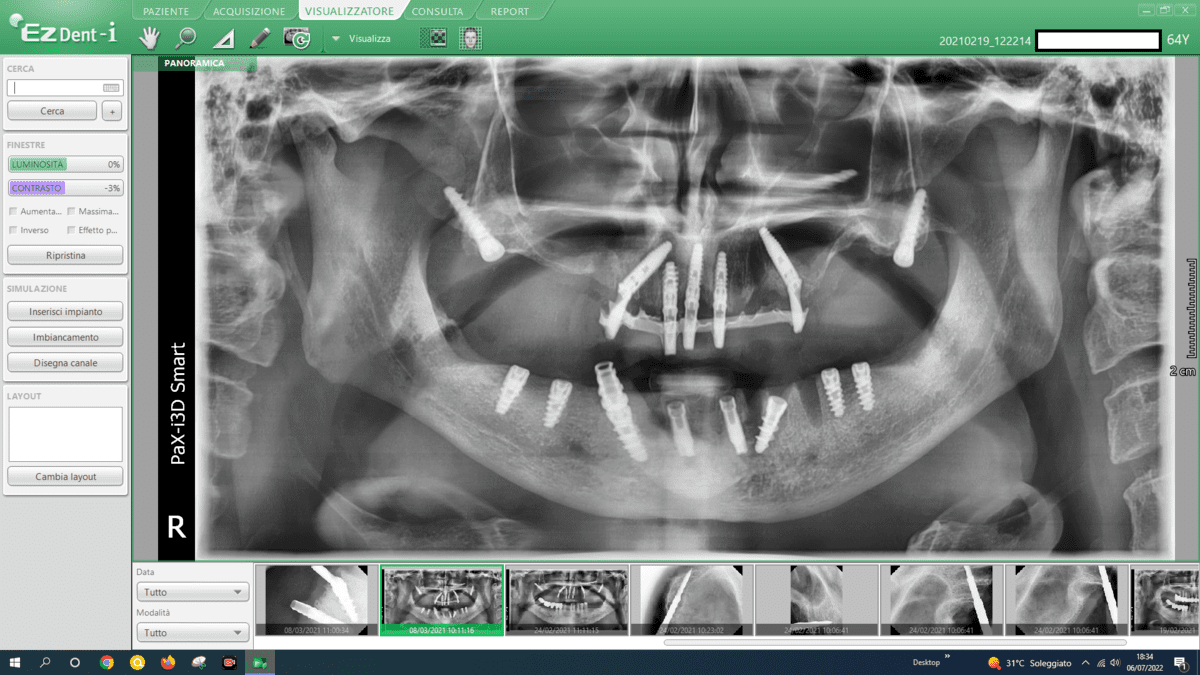

- Advanced Implant Techniques:

- Advanced implant techniques, such as Galileus Cerclage Sinus® mentioned in previous conversations, can offer innovative solutions for addressing atrophies. These techniques focus on strategically placing implants to optimize bone utilization.

In addressing mandibular atrophies, our approach revolves around utilizing advanced implant techniques that offer superior outcomes compared to traditional methods like autologous bone grafts. Here’s a breakdown of our considerations:

- Transverse Implants:

- We employ transverse implants, strategically placed across the mandible. This technique provides stability and support, avoiding the need for extensive bone grafting.

- Blade Implants:

- Blade implants are another key component of our approach. These implants are designed for efficient insertion, providing secure anchorage in atrophic areas without the challenges associated with autologous bone grafts.

- Grid-Like Subperiosteal Implants:

- Our practice utilizes subperiosteal implants configured in a grid-like pattern. This innovative approach optimizes bone contact, ensuring a strong foundation for the implants. This technique eliminates the necessity for autologous bone grafts and their associated complexities.

- Split Crest Procedures:

- Split crest procedures are implemented to widen the alveolar ridge, creating space for implant placement. This technique enhances bone volume and facilitates the successful integration of implants, avoiding the need for time-consuming autologous bone grafts.

- Avoidance of Autologous Bone Grafts:

- We intentionally steer clear of autologous bone grafts due to their drawbacks, including extended surgical procedures, heightened pain levels, and potential complications. Our chosen techniques are not only more efficient but also offer predictability, minimizing the risk of infections and ensuring a smoother recovery.

By embracing these advanced implant techniques, we prioritize patient comfort, reduce procedural complexities, and enhance the overall success and predictability of the treatment. Our commitment lies in providing innovative solutions that not only address mandibular atrophies effectively but also offer a more streamlined and reliable alternative to traditional approaches.